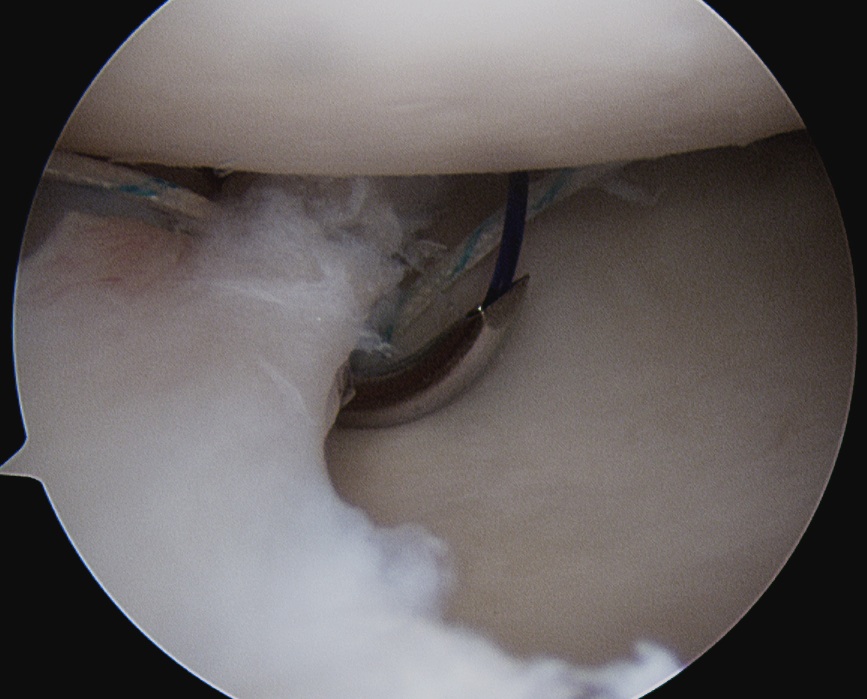

Technique arthroscopic anterior labral / Bankart repair

Vumedi arthroscopic Bankart repair video

Steps

Mobilize anterior labrum

Debride anterior glenoid to bleeding bone

Insert minimum 3 anchors between 5.30 and 3 o'clock

Repair capsulolabral tissue

Mobilize labrum

Labral mobiliser / rasp

- labral tear can be obvious, but may have partially healed or healed medially

- change camera to anterosuperior portal for better view

- mobilize until can see subscapularis muscle underneath

- need to be able to advance labrum medially and superiorly for repair

Debride anterior glenoid bone to bleeding bone

Insert anchors

Inferior anchor at 5.30 o'clock

- curved anchor guide / trans-subscapularis

- on rim of glenoid

Other anchors typically at 3 and 4 o'clock

Pass sutures and tie knots

Typically curved suture passers

Aim to tighten capsule medially and superiorly onto glenoid